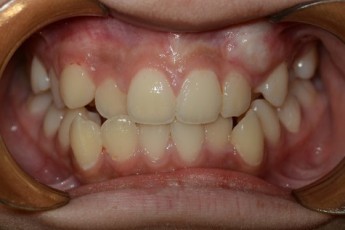

Before

After